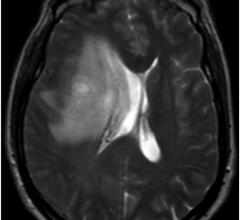

The radiology imaging channel includes technology news related to computed tomography (CT), digital radiography (DR / X-ray), ultrasound, magnetic resonance imaging (MRI), radiographic fluoroscopy (R/F), mammography, angiography, 3-D printing, contrast media injectors, molecular imaging, neurological imaging, pediatric imaging and radiation dose management.